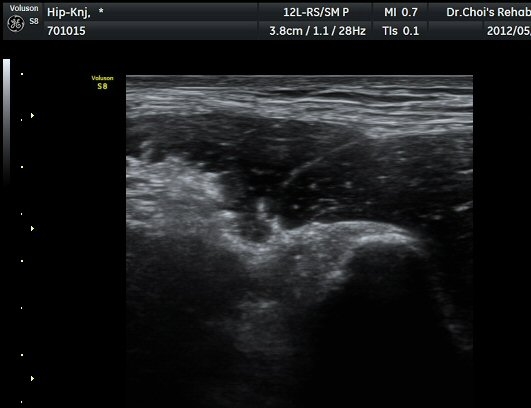

µÚÂÊ ´ëÅð ³»Ãø Ⱦ´Ü¸é°Ë»ç¿¡¼­ À̵ιڱ٠ÀåµÎ ¿ÜÃø¿¡¼­ ±ÙÀ°¼¶À¯¿Í ±Ù¸·¿¡ ÀÇÇØ Çü¼ºµÇ´Â

Á¤»óÀûÀÎ ±ÙÀ°ÀÇ ¸ð¾çÀÌ ¼Ò½ÇµÇ°í Àú¿¡ÄÚ º´º¯À¸·Î °üÂûµÈ´Ù(±×¸² 6). ŽÃËÀÚ¸¦ Á¶±Ý ¸»´ÜÀ¸·Î

À̵¿ÇÏ´Ï Àú¿¡ÄÚ º´º¯³»¿¡¼­ ±¹¼ÒÀûÀÎ ¼ö¾×Àú·ù°¡ °üÂûµÈ´Ù(±×¸² 7, 8).  À̵ιڱ٠ÀåµÎ Á¾´Ü¸é